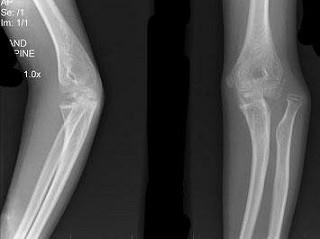

男,12岁,右前臂外伤后入院。结合图像,正确的诊断是?(?)A.Colles骨折B.孟氏骨折C.青枝骨折D.Smith骨折E.桡骨小头脱位

问题 男,12岁,右前臂外伤后入院。结合图像,正确的诊断是?(?)

选项 A.Colles骨折 B.孟氏骨折 C.青枝骨折 D.Smith骨折 E.桡骨小头脱位

答案 E